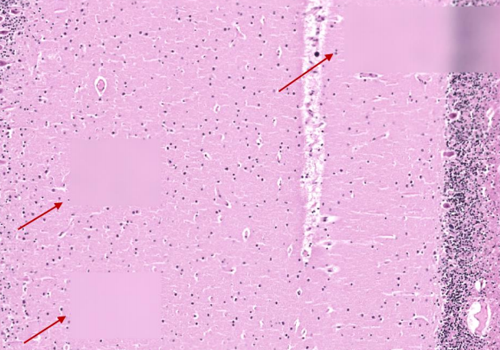

Problem: There are distinct horizontal and vertical seam lines on every image tile because either no background image was used, or the background image has uneven lighting. Solution: